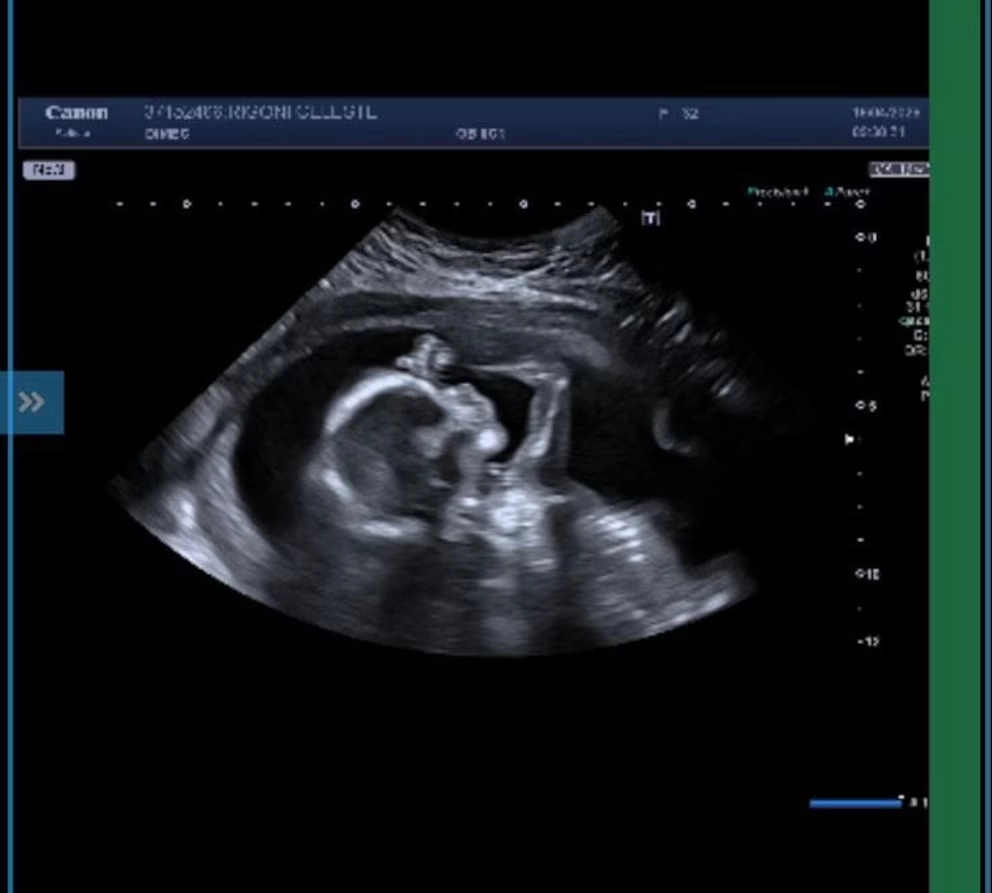

Se trata de Juan Reverdito, quien formó parte de la edición 2022 y que hoy vuelve a estar en el centro de la escena, pero por un motivo completamente distinto al juego. La novedad se conoció a través de redes sociales, donde comenzaron a circular imágenes que no tardaron en viralizarse: una ecografía y una foto familiar junto a su pareja, Celeste Rigoni, y su hijo.